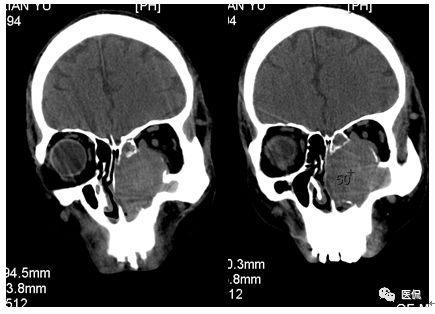

增强静脉期

CT平扫及增强示:左侧上颌窦及鼻腔可见软组织密度影,呈膨胀性生长,周围骨质压迫性吸收破坏,累及左眶,病灶密度不均匀,周边区可见点状钙化,增动脉期轻度强化,局部见小灶性稍高密度区,静脉期病灶内见不均匀明显强化,CT值最高达117HU,延迟期强化范围有所增大。

本例病灶较大,周围骨质可见吸收破坏,并累及眼眶,病灶内少量钙化,增强扫描具有一定特征性,表现为动脉期轻度强化,局部见小灶性稍高密度区,静脉期病灶局部呈明显强化,CT值最高达117HU,延迟期强化范围有所增大,呈延迟渐进性强化的特点,推测为病灶内出血所致。